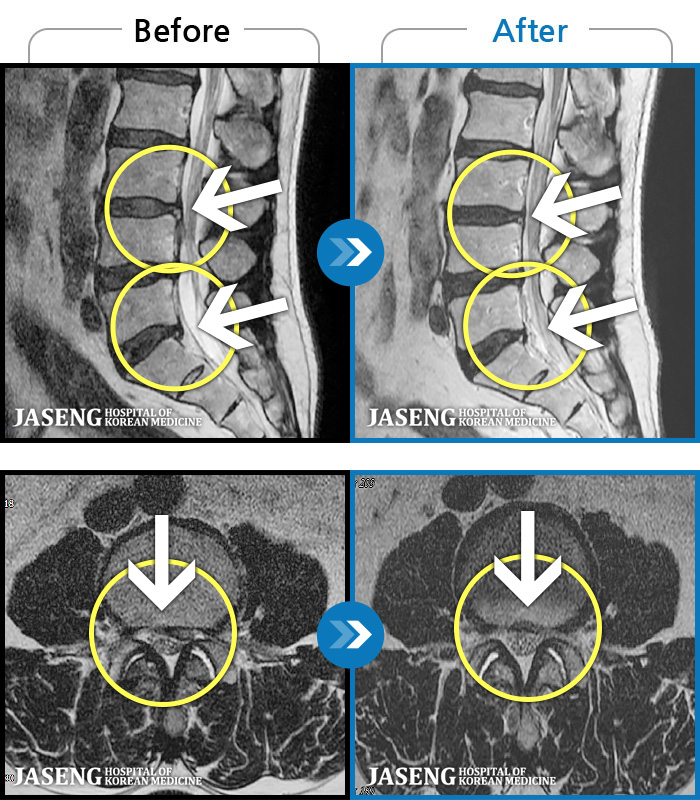

MRI ġ

1,301 MRI ũ ʸ Ȯϼ.